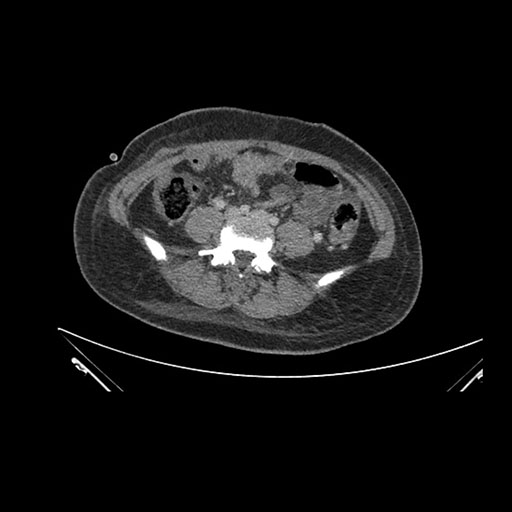

Axial Venous

Imaging analysis

Based on initial findings, which issue(s) would you be most concerned about?